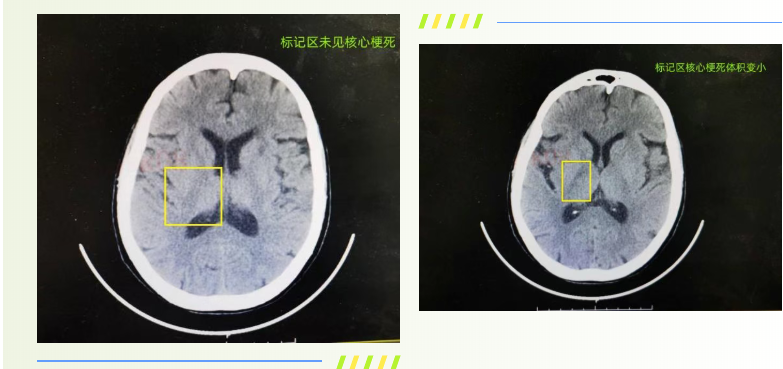

75岁的宋大娘因心慌、纳差、精神差入住泰安市第一人民医院心内科,老人既往有冠心病、充血性心力衰竭及心房颤动病史,长期口服利伐沙班进行抗凝治疗。入院当晚凌晨0时,宋大娘肢体活动一切正常,如厕后正常入睡,谁料次日晨7时醒来后,突发言语不清、左侧肢体活动障碍的症状。神经内三科医师接到会诊请求后第一时间赶往病房,结合症状快速判断为急性缺血性脑卒中(醒后卒中),为患者进行NIHSS评分达12分,情况十分危急。神经内科介入团队迅速响应,神经介入科主任王伟、神经内三科副主任张松第一时间确定诊疗方案,当即启动脑卒中绿色通道,快速联系核磁共振室,为患者紧急行颅脑MRI+MRA 检查。检查结果提示患者 DWI/FLAIR 不匹配,存在缺血半暗带,颅脑MRA 显示右侧颈内动脉闭塞,这意味着患者脑部仍有可挽救的脑组织,为后续精准救治提供了关键依据。

结合宋大娘的心房颤动病史及影像学检查表现,团队判断其 TOAST 分型为心源性栓塞型,患者末次正常时间为凌晨0时,影像学指征明确,具备急诊溶栓及介入治疗的条件。但考虑到患者长期口服利伐沙班,治疗方案的选择需更加谨慎,王伟主任与患者家属进行充分、细致的沟通,全面讲解了机械取栓术、桥接治疗及保守治疗三种方案的获益与潜在风险,家属商议后决定采取机械取栓术。就在术前查体时,患者左侧肢体活动较前出现一定恢复,家属见状产生了犹豫,王伟凭借丰富的临床经验判断,这一情况大概率是栓子部分逃逸所致,患者仍存在再栓塞及病情突然加重的风险,随即建议为患者行急诊脑血管造影+必要时机械取栓术,家属表示理解并同意。术中造影结果证实了医师的判断,患者右侧颈内动脉依旧处于闭塞状态,且存在大量栓子负荷。为了让家属更全面地了解手术情况,张松再次与家属沟通,详细说明手术路径、具体操作方式、费用构成以及相关医保报销政策,在家属充分知情并同意后,介入团队立即为患者开展机械取栓术。整个手术过程高效顺利,历时不足1小时便成功完成,术后宋大娘的四肢活动即刻恢复正常,言语也变得流利,术后次日复查颅脑CT显示,患者核心梗死区体积较前明显缩小,救治效果十分显著。